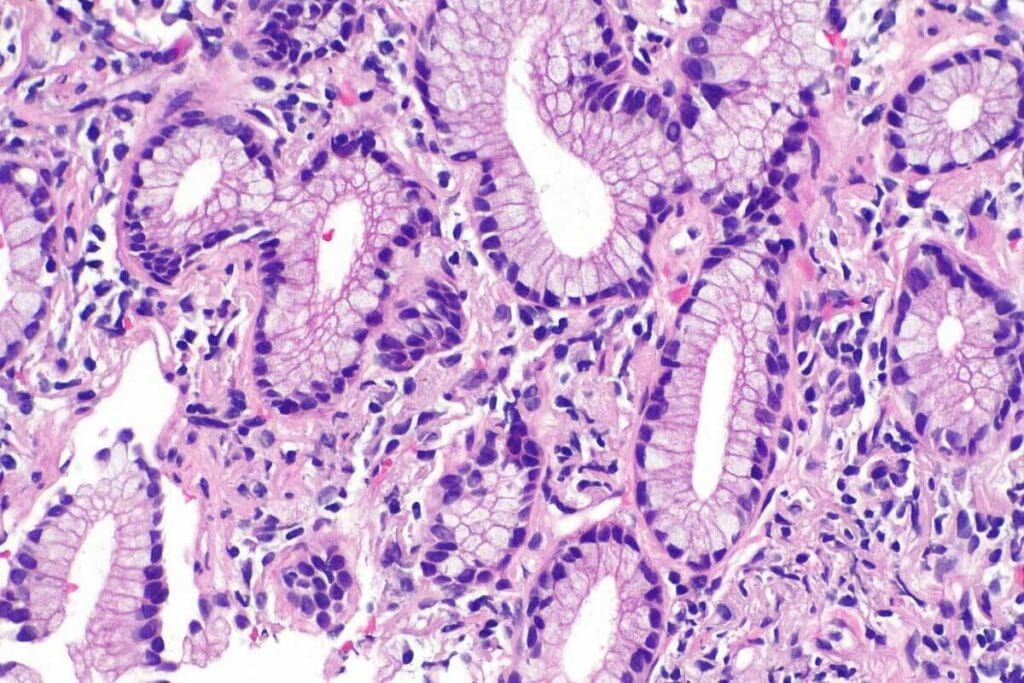

Adenocarcinoma starts in gland cells. It can happen in places like the breast, colon, lung, and prostate. Studies show it’s the most common cancer in some groups. Where it occurs affects how it’s treated.

Because it starts in gland cells, adenocarcinoma can show up differently. For example, lung adenocarcinoma is not the same as breast adenocarcinoma. This means each type needs its own treatment plan.

Adenocarcinoma starts in glandular cells. These cells are found in places like the breast, colon, and lung. It’s different from other cancers because it comes from glandular tissue.